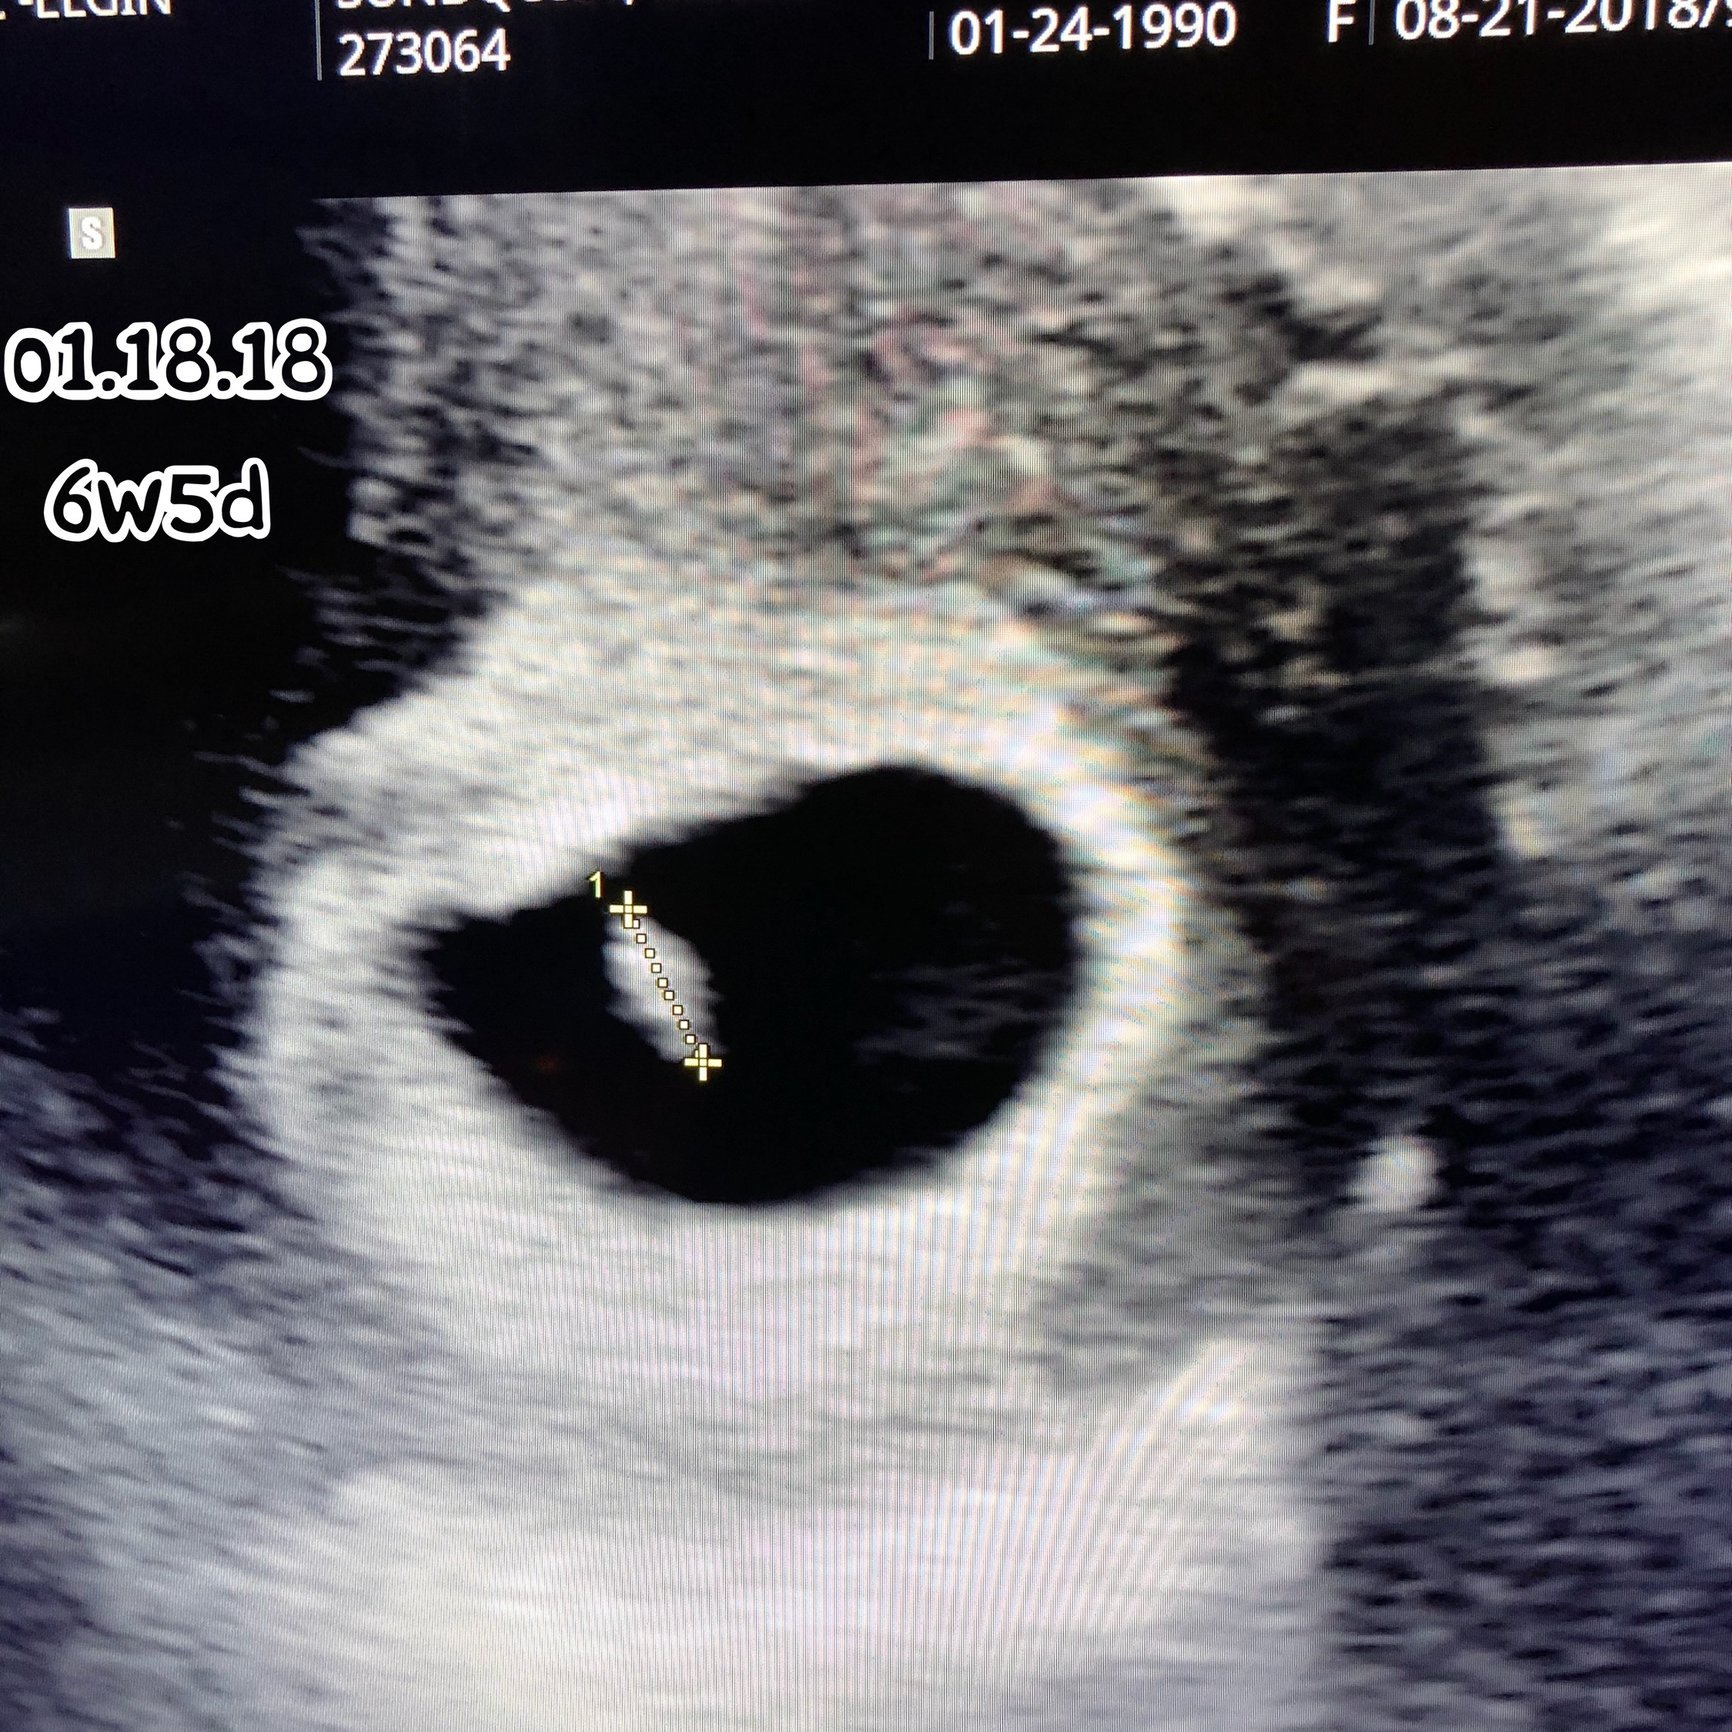

2 Cycles of Femara, Ovidrel, & Progesterone= BFP #3 DS born 5/17/16 TTC #2 March 2017 (initially med free) BFP #4 8/14/17 *natural cycle* EDD= 4/25/18, MC @5-6w D&C 9/22/17 BFP #5 12/29/17 w/ Femara/Ovidrel/Progesterone/Synthroid, EDD= 9/11/18 found out 1/18 ITS di/di TWINS!!! DS and DD born 8/21/18

BFP #5 12/29/17 w/ Femara/Ovidrel/Progesterone/Synthroid, EDD= 9/11/18 found out 1/18 ITS di/di TWINS!!!

DS and DD born 8/21/18